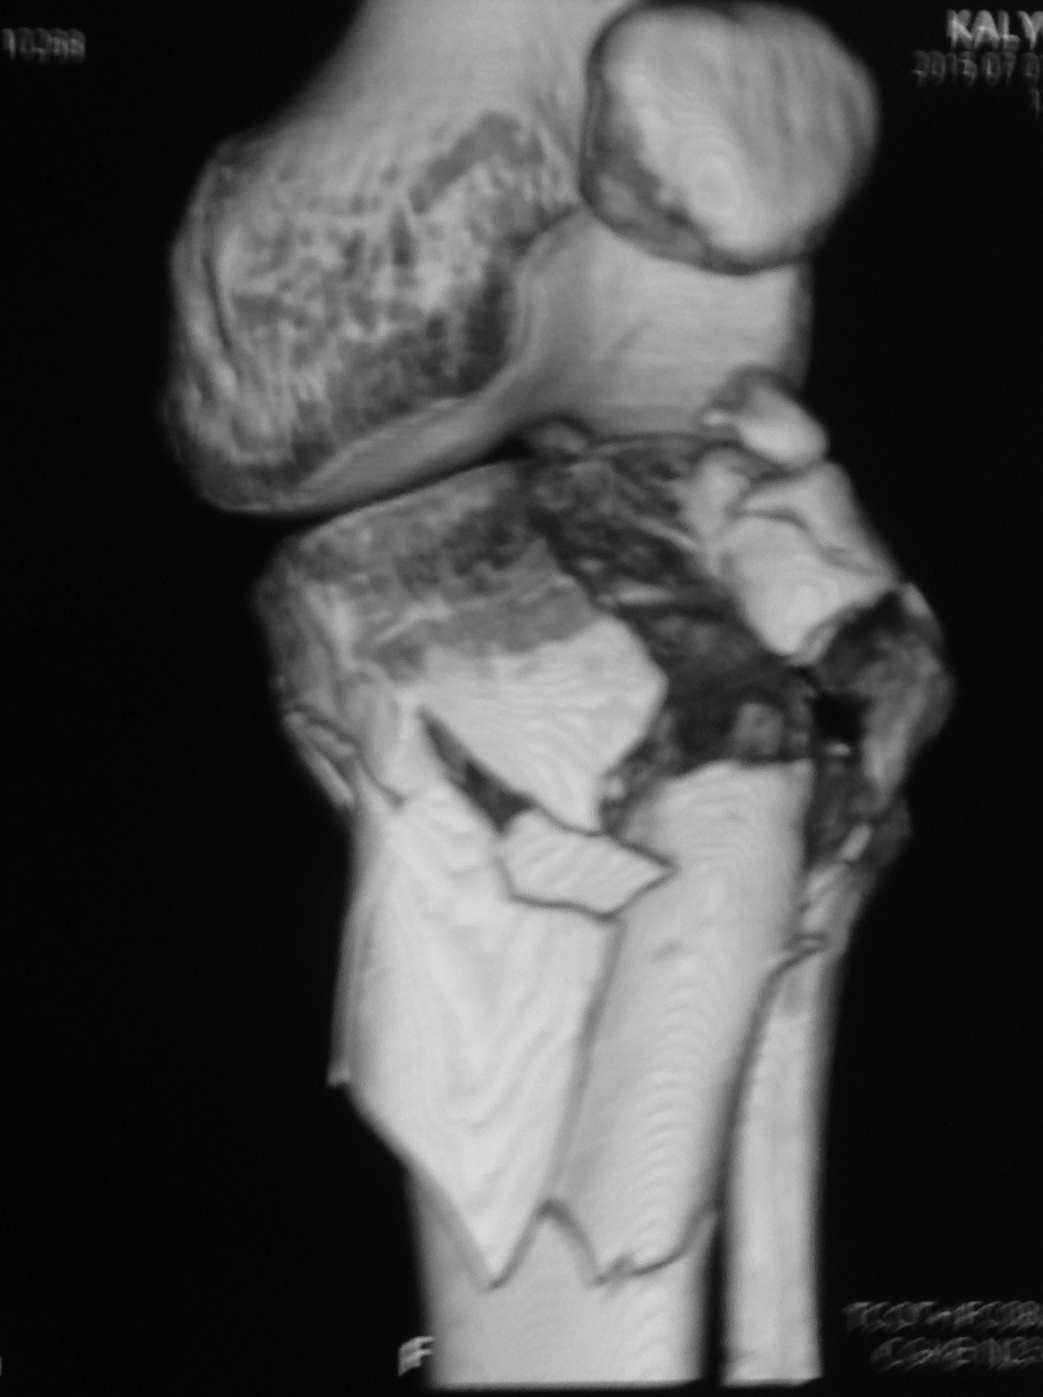

Серия КТ сканов в аппарате

Добрый день, коллеги! Повреждение вертлужной впадины вероятнее всего 62-А1.2 чистый переломовывих, оскольчатый перелом задней стенки, при этом внутрисуставной фрагмент, является частью артикулирующей поверхности ацетабулюм, а следовательно его необходимо извлечь и поместить на место, иначе мозаика может не собраться. Про FAI временно можно не вспоминать (не до него), поскольку наиболее тяжелое повреждение голени требует адекватного вмешательства.На представленных рентгенограммах таза после операции все отлично, полную картину даст КТ.

Голень-41-С3.1 - полный внутрисуставной и метафизарный оскольчатый перелом с доминантным повреждением наружного мыщелка, с импрессией центральной части плато. Первичная тактика полный респект по АО и ОТА. на фоне лигаметотаксиса выполнено КТ, которое четко детализирует повреждение и определяет дальнейшую тактику.

Основная проблема не бугристость, а внутрисуставное повреждение латерального мыщелка с импрессией центральной части. С большей вероятностью, есть паракапсуллярное продольное повреждение наружного мениска.